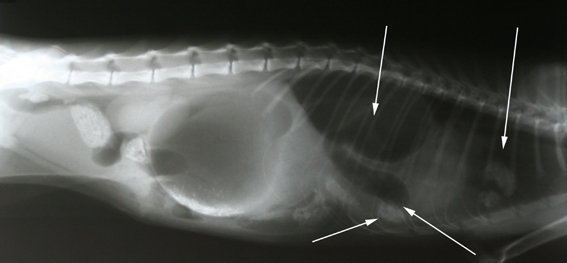

We hebben om die reden besloten opnieuw röntgenfoto’s te maken.

Op deze foto bleken ineens darmstructuren te zien in de borstholte, er was dus sprake van een scheur in het middenrif.

Blijkbaar was het middenrif toch beschadigd bij het ongeluk, zonder dat er daadwerkelijk een gat aanwezig was. In de loop van de week is het beschadigde deel kapot gegaan en is er een breuk ontstaan (mocht er een gat geweest zijn tijdens de vorige operatie, en er dus een verbinding zijn tussen de buikholte en de borstholte, dan hadden we namelijk tijdens die operatie een klaplong bij Otje veroorzaakt door de buikholte te openen).